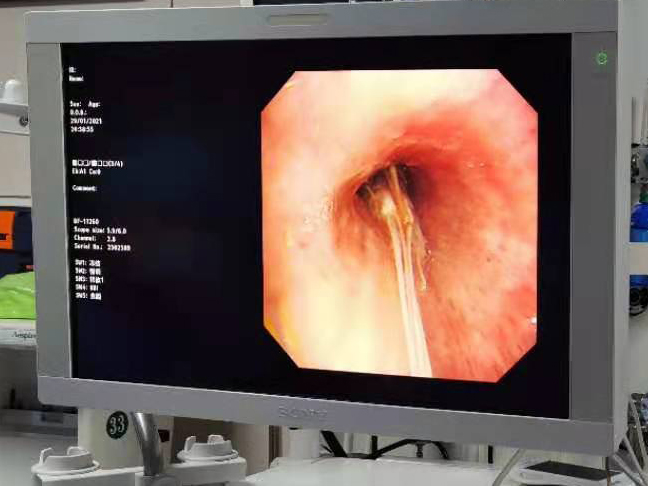

考虑到呛入气管内的白虾体积较大,无法经鼻腔取出,我们为该患者进行了经口气管镜检查。

左主支气管内可见白虾的头部,长长的虾须延升至隆突处

考虑到白虾质地较软,异物钳钳夹过程中可能导致虾头与身体分离、碎裂,导致取出困难,介入团队在商议后决定给患者进行冷冻取异物术。